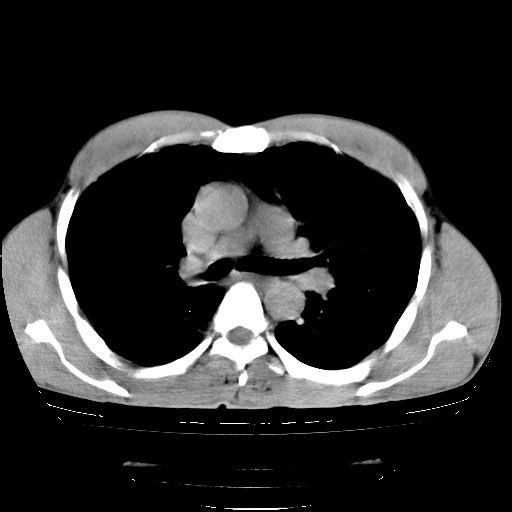

以下是引用yangyudong333在2008-4-29 5:38:00的发言:[br]比较典型的矽肺结节.支持[br]诊断依据:[br] 1.x线表现:[br] ①典型矽肺为多发直径 1~3mm 小结节,即矽结节,由胶原纤维和硅尘构成,可融合成团块,好发于上肺。[br] ②团块周围常有肺大泡。[br] ③胸内淋巴结增大、钙化。如肺门淋巴结呈蛋壳样钙化有助于与其他尘肺区别。[br] ④胸膜常广泛粘连、增厚。[br] 2.ct表现[br] ①两肺散在大小较为一致的小结节影,其密度较高,边界清楚。[br] ②小结节可融合为较大团块影,直径约 1cm ,甚至可达 10cm以上,易发生在上叶。[br] ③小结节周围常并有小叶中心气肿或弥漫性肺气肿。

以下是引用liuyue在2008-4-28 22:30:00的发言:[br]比较典型的矽肺结节.[br]请结合临床及化验除外矽肺合并肺结核之可能.